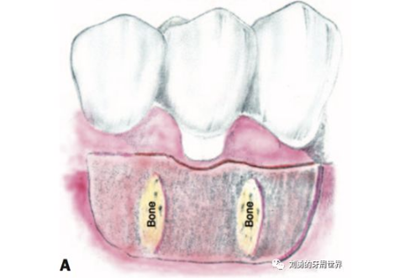

為了避免上述的問題,因此有人提出來可以將受區(qū)制備成全厚瓣,這樣將來齦瓣直接放在骨面,就不會(huì)有那些可移動(dòng)纖維的存在了,術(shù)后齦瓣更加穩(wěn)定。

比如下圖:

但是該方法有個(gè)弊端,那就是受區(qū)沒有骨膜了,齦瓣的血供會(huì)變差,有人提出來了改良的方法,就是保留骨膜,但是為了減少骨膜上纖維的移動(dòng)性,對(duì)骨膜進(jìn)行垂直向的全厚層切透,減少骨膜的動(dòng)度,這就是垂直骨開裂的改良方法,如下圖: